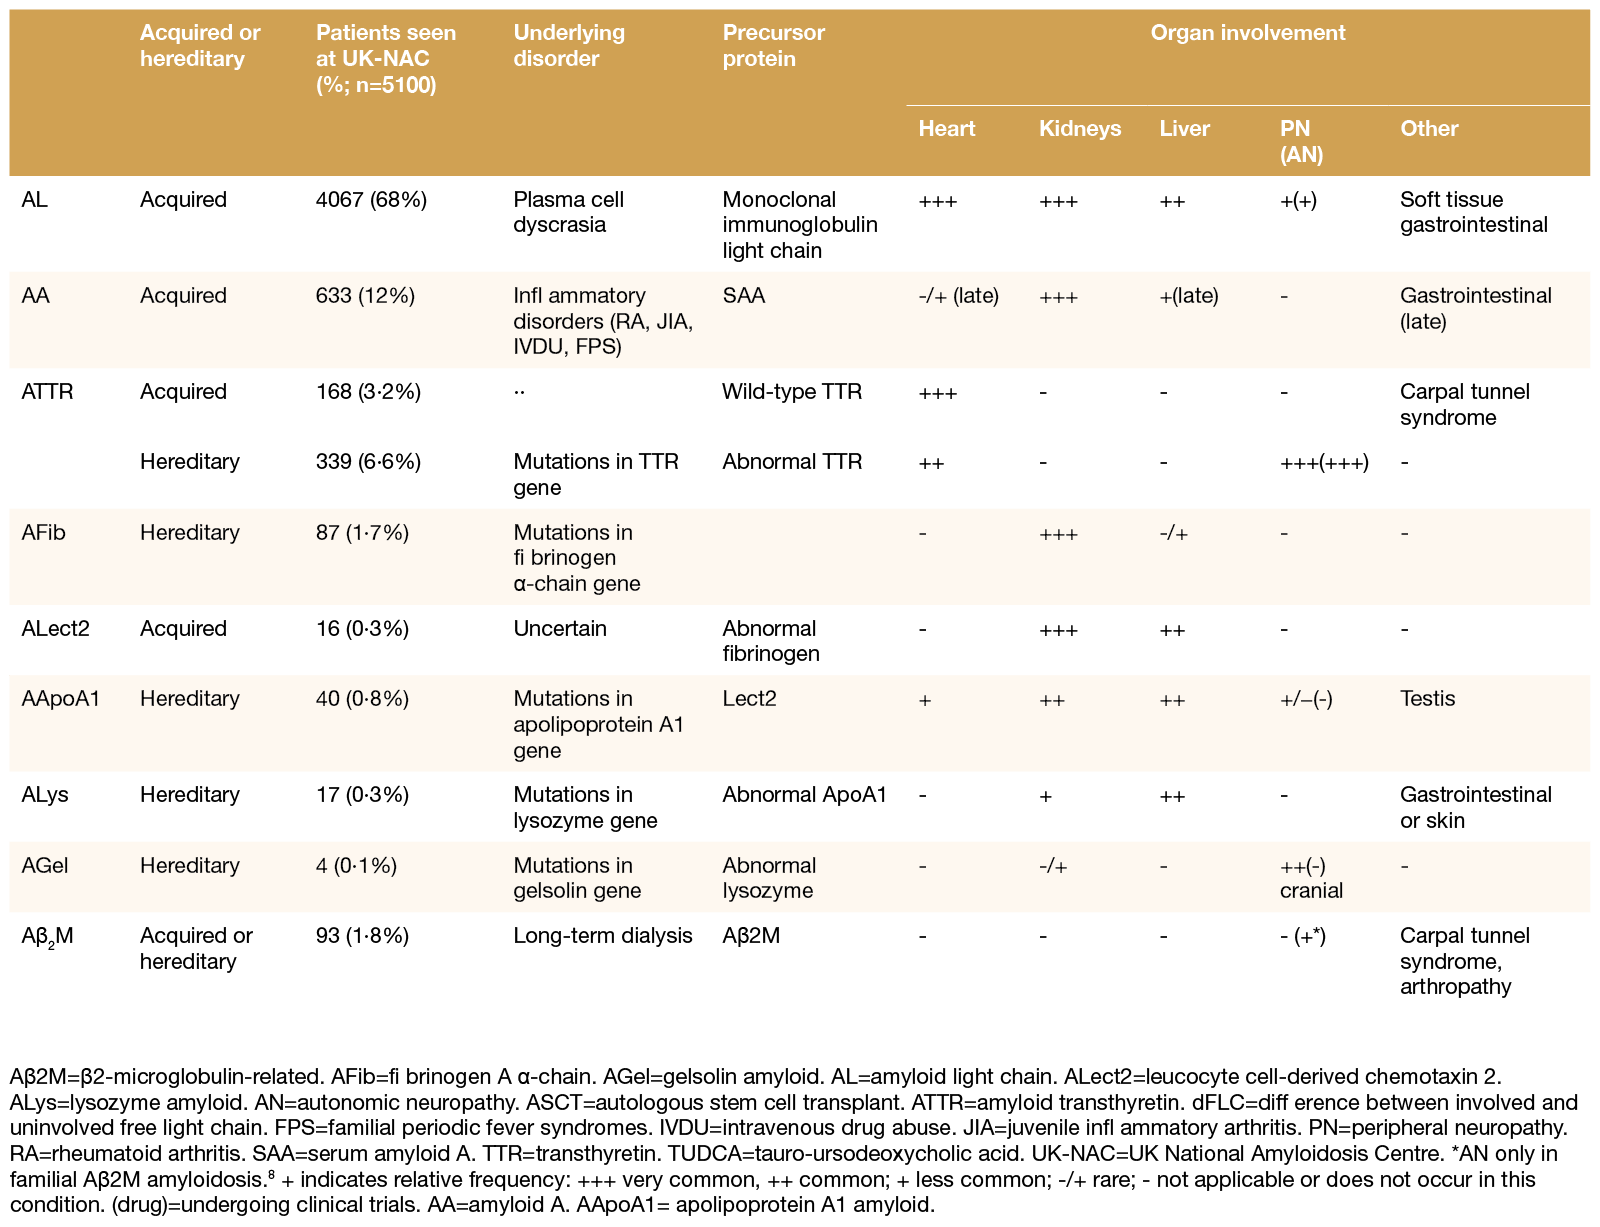

Een zeer uitgebreid overzicht biedt onderstaande tabel waarin de frequentie van verschillende types amyloïd onder 5.100 personen met amyloïdose of amyloïdogene mutaties beoordeeld door het National Amyloidosis Centre (NAC) in het Verenigd Koninkrijk tussen 1987 en 2012 staat vermeld.106